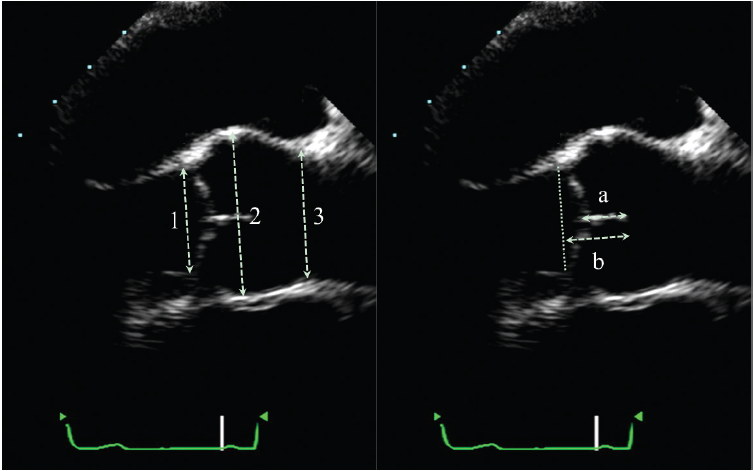

Fig. 2. Three-dimensional transesophageal echocardiography (3D TEE) analysis of the aortic root. From the 3D zoom datasets, 2 long axis views of the aortic valve (A, B) and the short axis view orthogonal to these long ... Read Here